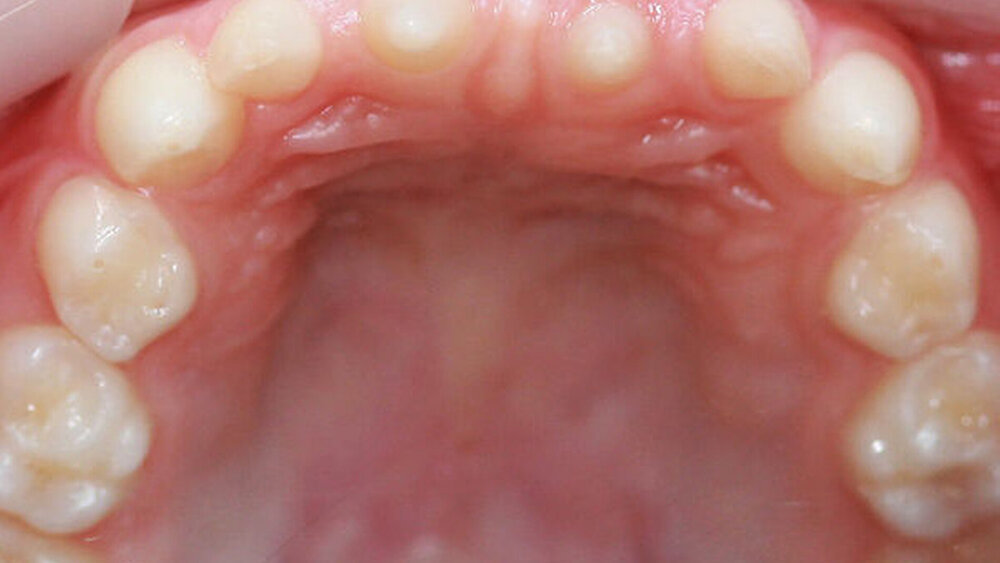

Ein siebenjähriges Mädchen wird im August 2017 aufgrund auffällig vieler Nichtanlagen in unsere Praxis für Kinder- und Jugendzahnheilkunde in Beckum überwiesen. Extraoral zeigte es keine markanten Auffälligkeiten, die Gesichtssymmetrie war weitgehend harmonisch, das Haar dunkel und dicht gewachsen. Intraoral zeigte sich ein Wechselgebiss in der ersten Phase des Zahnwechsels mit einem permanenten Zapfenzahn 11 sowie einem weiter palatinal stehenden Zapfenzahn 21 mit dem persistierenden Milchzahn 61. Die Molaren (16, 26, 36 und 46) waren in die Zahnreihen eingeordnet (Abbildungen 1 und 2). Das gesamte Gebiss war kariesfrei, die häusliche Mundhygiene gut.